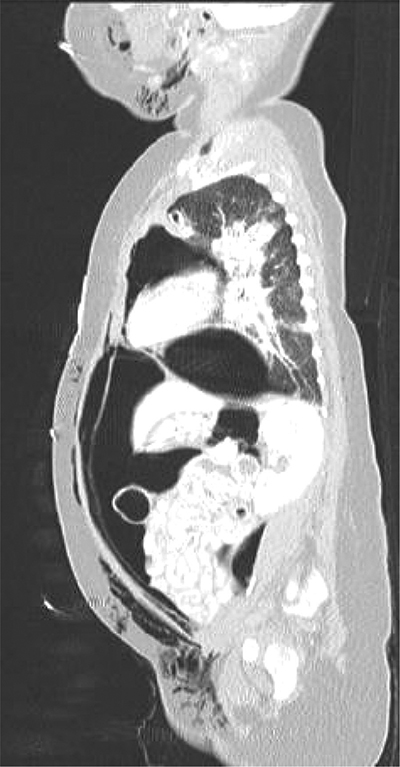

At 14 weeks of corrected age, the patient developed an episode of bronchiolitis. Thoracic radiography showed multiple pulmonary opacities and an air bronchogram suggesting pneumonia (Figure 1), treated with antibiotics, and abdominal radiography showed hyperinflation (Figure 2).

Figure 1

Chest antero-posterior radiograph.

Multiple pulmonary opacities and an air bronchogram suggesting pneumonia.